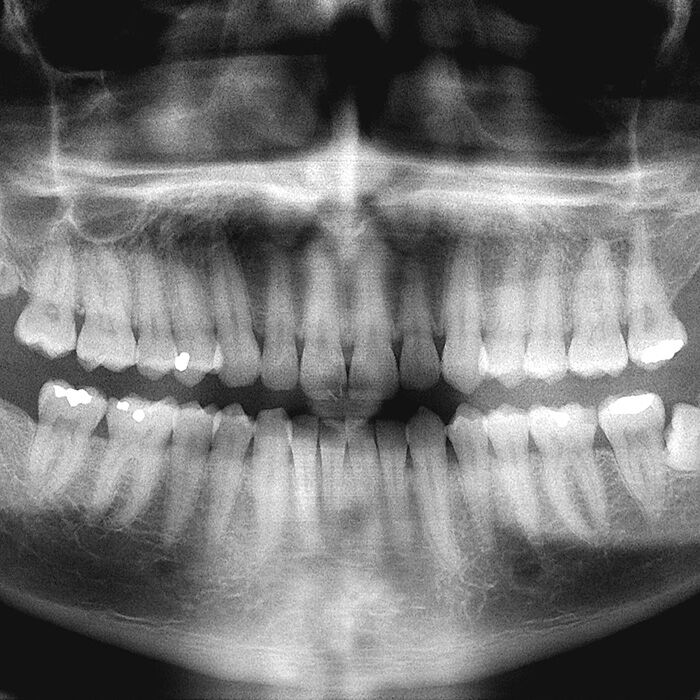

Wir verwenden in unserer Praxis sowohl für die Einzelbild- wie auch für die Panorama-Aufnahme (Darstellung des gesamten Ober- und Unterkiefer mit angrenzenden anatomischen Strukturen) ausschließlich die digitale Aufnahmetechnik. Statt eines Films, der von den Röntgenstrahlen belichtet wird und anschließend entwickelt werden muss, kommt beim digitalen Röntgen ein spezieller Sensor zum Einsatz, der die auftreffenden Strahlen in digitale Signale umwandelt. Durch den Einsatz von digitalen Röntgenanlagen reduziert sich für Sie die Strahlenbelastung um bis zu 90% gegenüber herkömmlichen Röntgengeräten. Anschließend kann das Bild auf dem Monitor im Behandlungszimmer sofort betrachtet und ausgewertet werden.